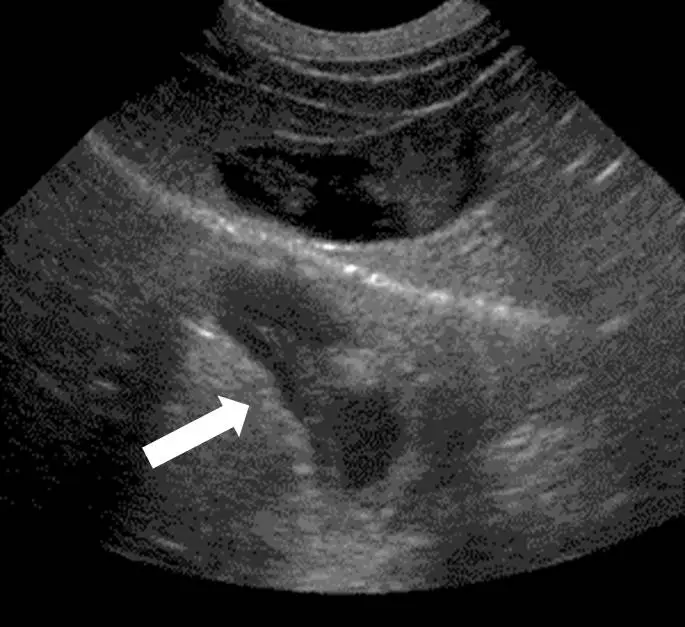

本題超音波圖像為右上腹掃描(right upper quadrant scan),可觀察到以下特徵:

- 上方區域:顯示正常肝臟實質(hepatic parenchyma),呈現均勻的中等回聲紋路;中央可見一黑色無回聲(anechoic)的橢圓形結構,為膽囊(gallbladder)。

- 中央強回聲弧線:橫跨圖像中部有一條明亮、高回聲的弧形線,為橫膈膜(diaphragm)與下方肺部-空氣界面,這是超音波波束的強反射面。

- 下方區域(白色箭頭指示):橫膈膜下方出現一片與上方肝臟實質高度對稱、外觀相似的回聲紋路區域。這並非真實組織,而是肝臟影像被「鏡射」到橫膈膜另一側所產生的假影。

關鍵識別特徵:真實肝臟在橫膈膜上方,而下方出現的「肝臟」對稱影像即為鏡面效果假影。白色箭頭明確指向此鏡射區域。若為音影則是強回聲體後方的無聲黑色區域;若